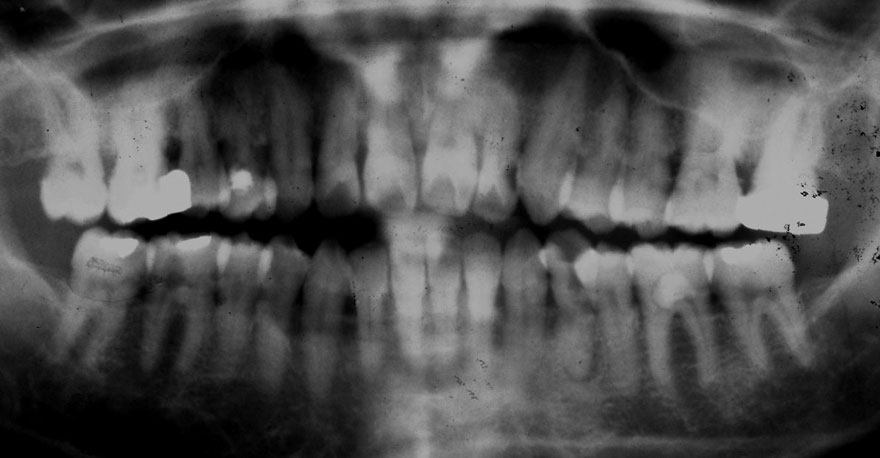

初診時 40歳 女性 平均歯槽骨喪失量:5.24mm

20年後 60歳

平均歯槽骨喪失量:5.79mm

21年間喪失量:-0.55mm

年間喪失速度:-0.027mm

(ケア頻度:1.23ヵ月ごと)